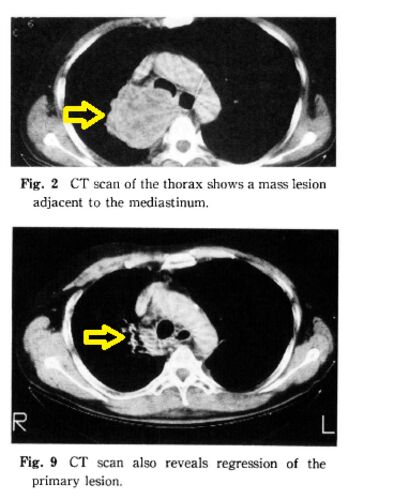

こんにちは。 以前の記事で、「がん(悪性腫瘍)」の増大速度はまちまちで、全ての悪性腫瘍が急速に増大することはなく、増大速度が遅いもの、増大速度が非常に遅いもの、大きくならないもの、自然に縮小するものがあるとお伝えしました。 検査で「癌かもし…